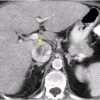

RCC

» Thông tin: Nữ giới – 69 tuổi.

» Lâm sàng: Đái máu.

# Ung thư biểu mô tế bào thận phải (Renal cell carcinoma – RCC) / Huyết khối tĩnh mạch chủ dưới.